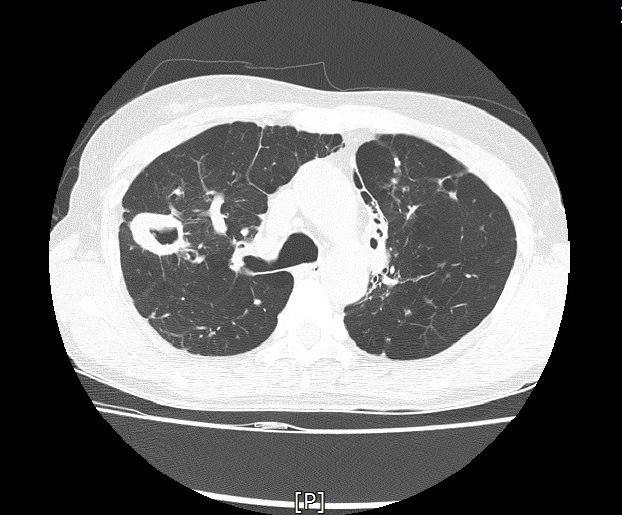

기관지확장증의 CT 사진